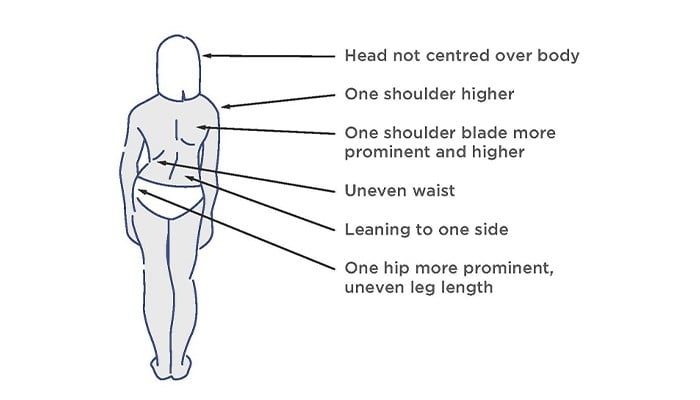

يمكن ملاحظة اعوجاج العمود الفقري في البداية من خلال التغير في مظهر ظهر الطفل. يمكن أن تشمل الأعراض ما يلي:

- العمود الفقري منحني بشكل واضح.

- كتف واحد أعلى من الآخر.

- بروز الورك أو الخصر بشكل غير متساوٍ؛ يبدو أكثر بروزا من الآخر.

- القفص الصدري بارز من جانب واحد – ويُعرف أيضًا باسم “السنام الضلعي” – وهو ملحوظ بشكل خاص من الخلف.

- صعوبة في الوقوف بشكل مستقيم.

- ألم في الظهر.

- اختلاف في طول الساق.

- بروز أحد جانبي القفص الصدري.

- ألم في الساقين أو على شكل دبابيس وإبر، ناجم عن الضغط على الأعصاب.

كل منحنى جنف فريد من نوعه. قد ينحني العمود الفقري إلى اليسار أو اليمين ويمكن أن يحدث في أجزاء مختلفة من العمود الفقري. إذا كان في منطقة الصدر يسمى الجنف "الصدري"، بينما إذا كان في الجزء السفلي من العمود الفقري يسمى الجنف "القطني". ومن الممكن أيضًا أن يكون هناك منحنيان؛ وهذا ما يسمى انحناء مزدوج وقد يبدو العمود الفقري على شكل حرف "S" من الخلف. ومن الممكن أيضًا الحصول على المزيد من المنحنيات التعويضية في أعلى وأسفل العمود الفقري. نظرًا لأن الجنف هو حالة ثلاثية الأبعاد ويحاول العمود الفقري دائمًا التعويض، فهناك العديد من الاختلافات المحتملة في المنحنيات. ومع ذلك، فإن المنحنى الأكثر شيوعًا هو المنحنى الصدري الأيمن.